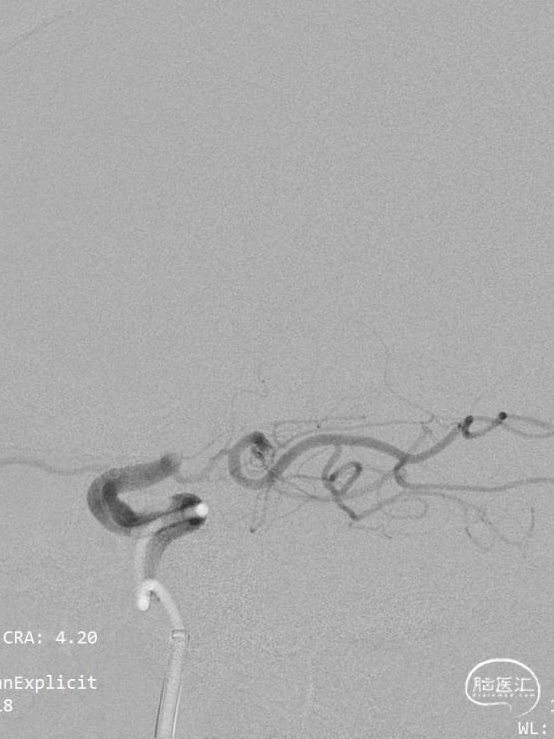

经过抽吸导管抽吸后造影见颈内动脉通畅,大脑前动脉显影,但大脑中动脉仍然闭塞。

0.021in Headway微导管超选越过闭塞段后微导管造影。

透视下可见Syphonet®取栓支架通体显影,有利于观察支架形态。